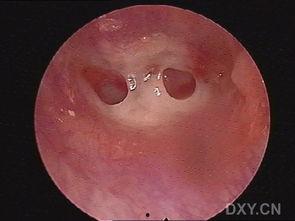

那是一个阳光明媚的午后,我正走在回家的路上,突然,一辆自行车从我身边呼啸而过。我下意识地躲闪,却没料到,那辆自行车上的恶人竟然故意撞向我。一阵剧痛袭来,我摔倒在地,耳膜被撞穿孔,鲜血直流。